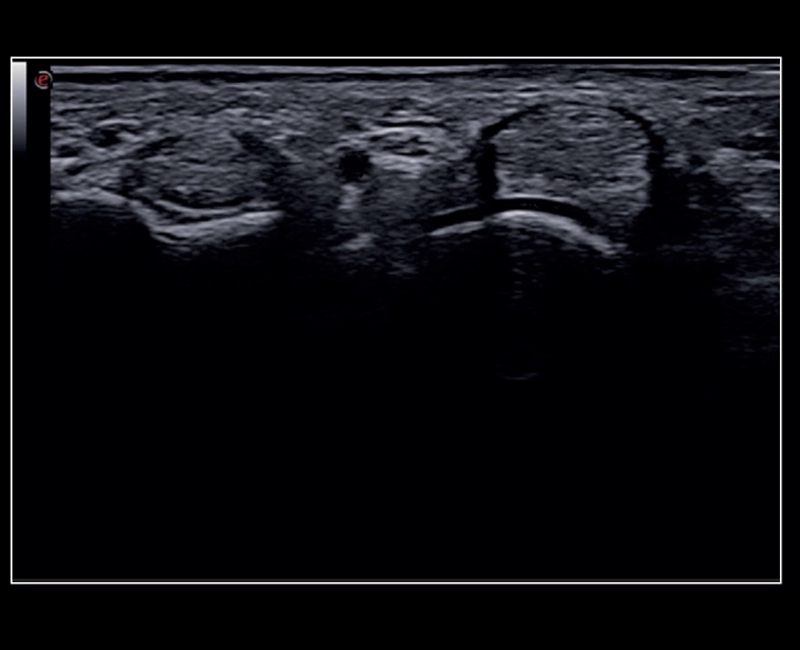

MyLab™9 Platform - Very-superficial linear imaging with Power Doppler algorithm

MyLab™9 Platform - Very-superficial linear imaging with Power Doppler algorithm